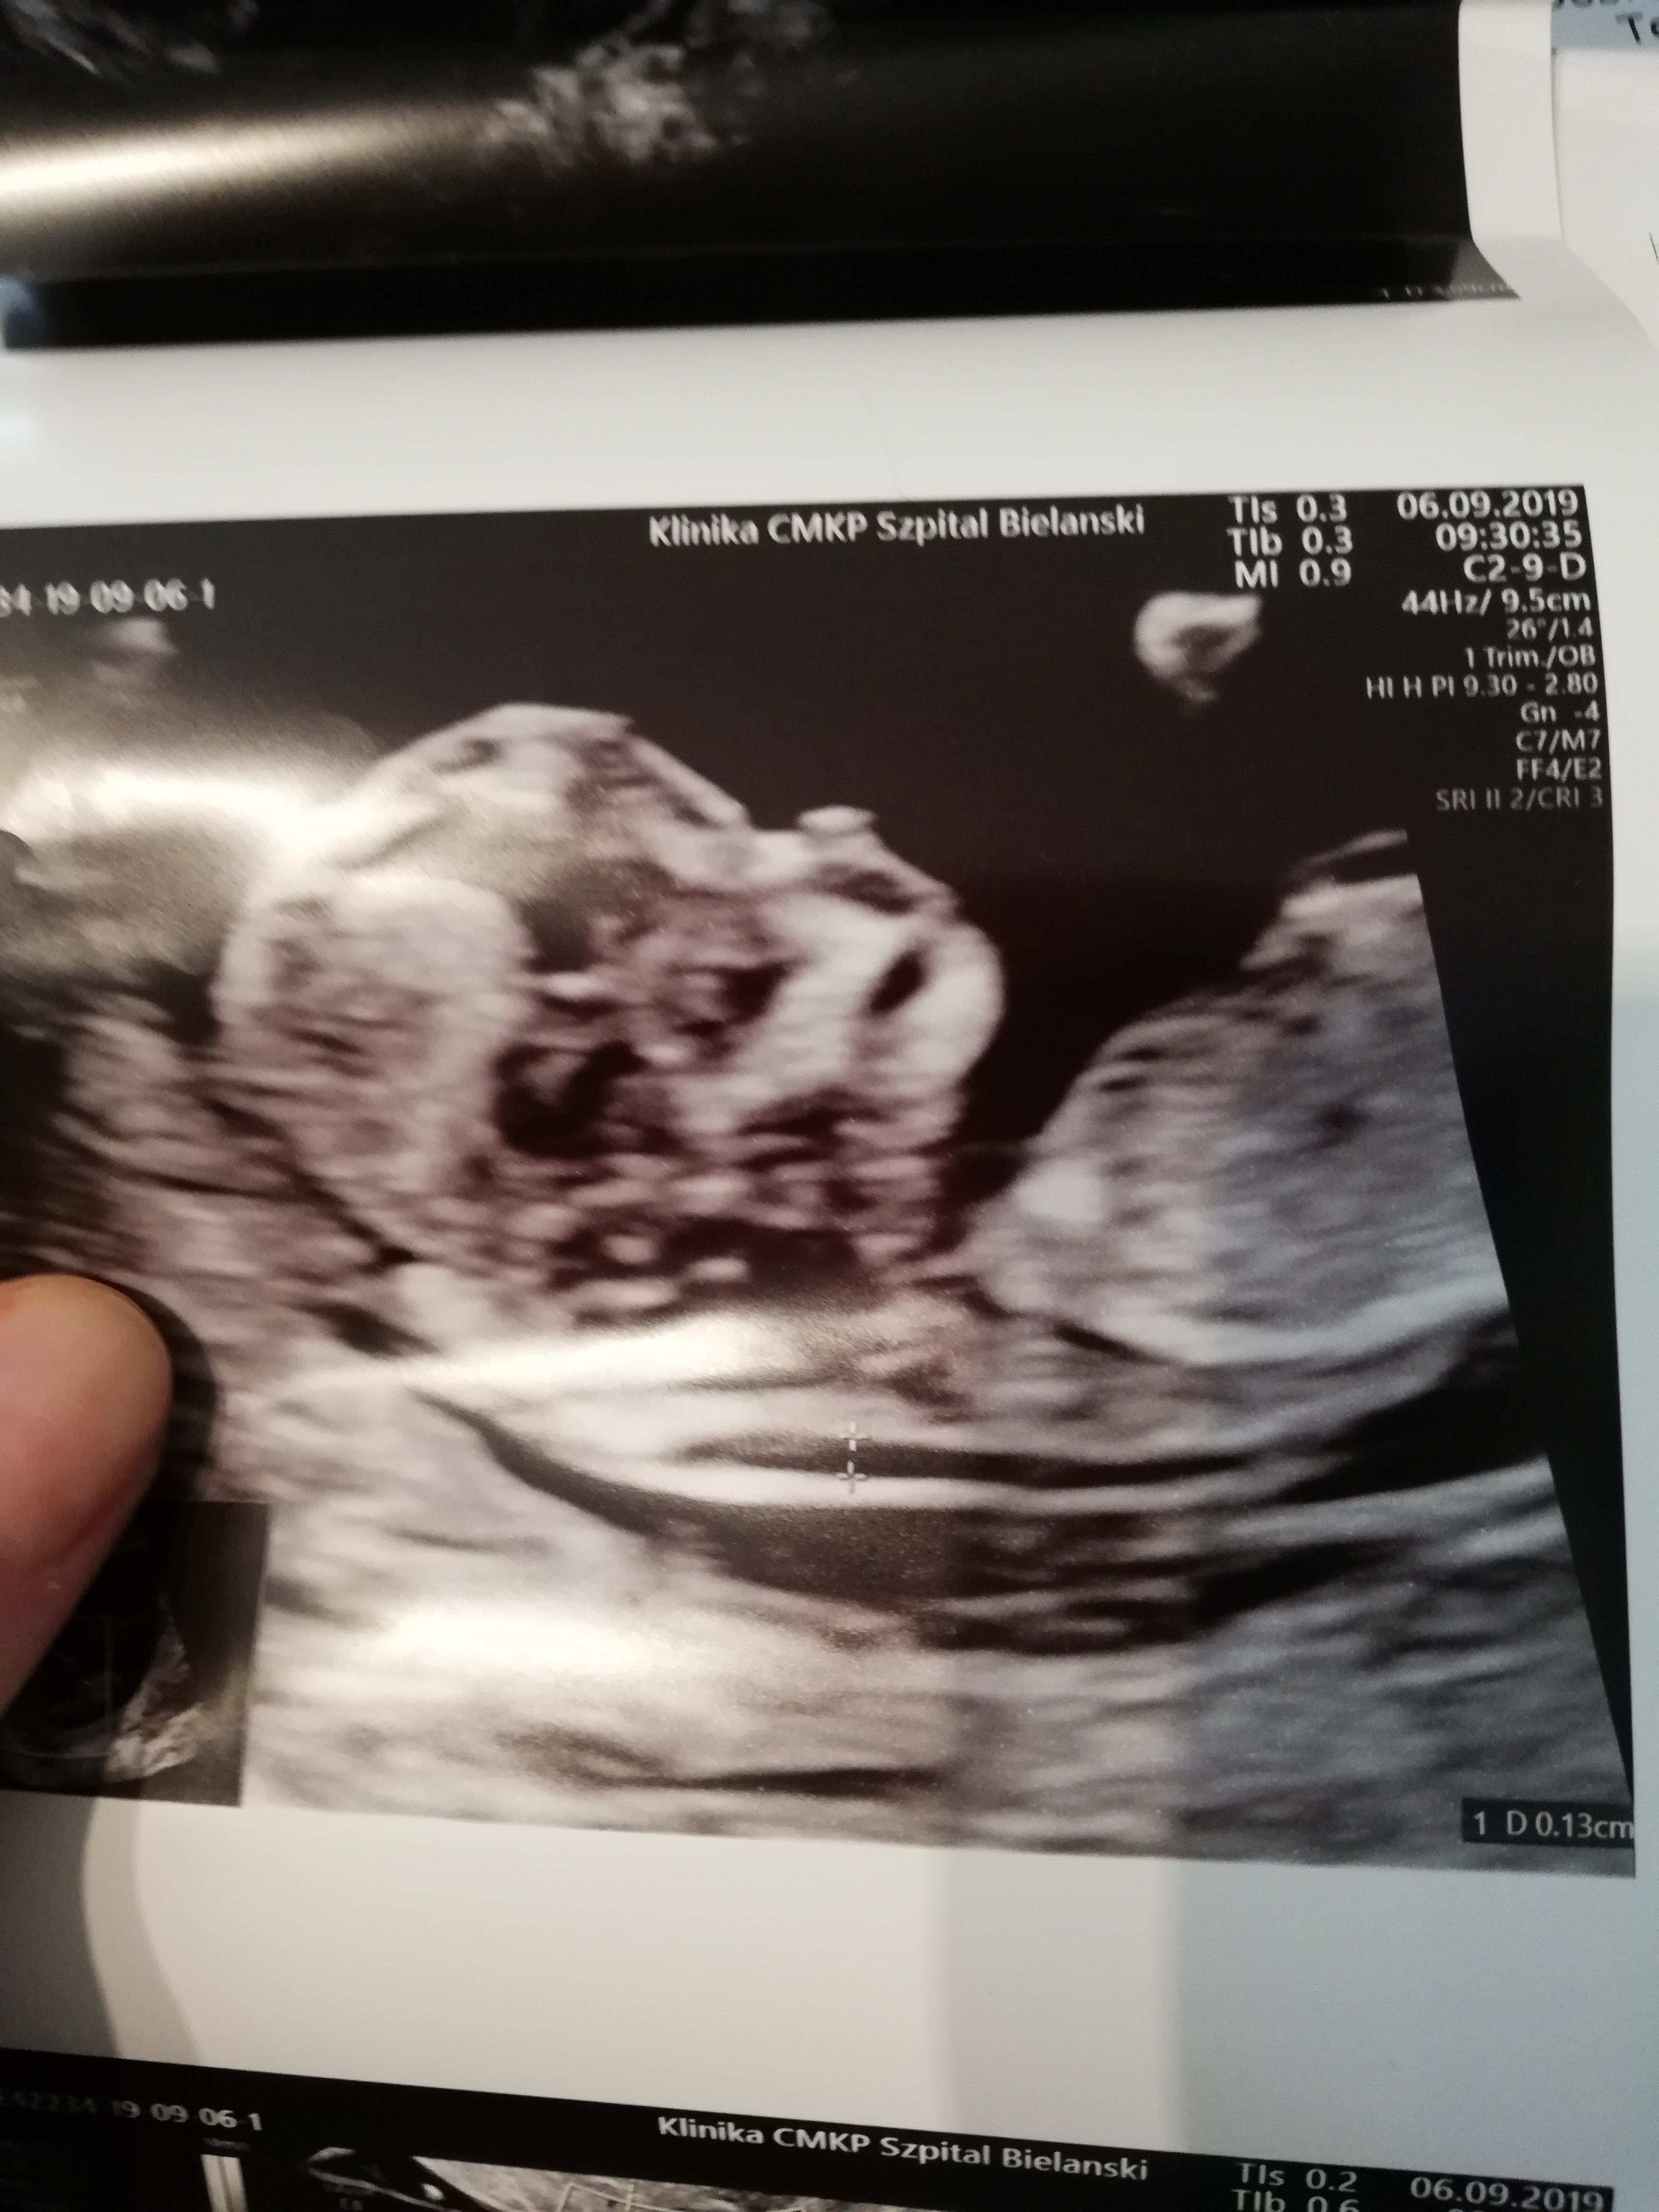

Melduję się po prenatalnym USG. Wszystko jest dobrze. Mam tylko do dziewczyn pytanie ile mialyscie DV PI (przepływy)? To miało byś istotne u mnie ale nie mogłam się już dopchac do mojego lekarza i nie wiem jakie są normy na necie też nic nie pisze

12 i 2 dni